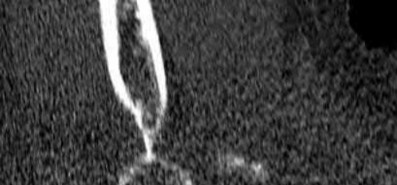

A 26-year-old male sustains an elbow injury after a fall from a skateboard resulting in valgus and supination forces across the left elbow. A CT scan of the left elbow is shown in Figures A through D. This fracture pattern is most commonly associated with what other traumatic elbow pathology?

The clinical presentation is consistent with a coronoid tip fracture. This fracture pattern is associated with a radial head fracture and posterolateral ulnohumeral dislocation - together making up the terrible triad injury.

A terrible triad injury is the result of a valgus and supination injury and involves posterolateral elbow dislocation or lateral collateral ligament injury, radial head fracture, and fracture of the coronoid process. The elbow may dislocate postero-laterally with the anterior bundle of the MCL intact, but if the MCL is injured it is typically the last structure to fail. The coronoid fracture is typically a small fragment isolated to the tip. This is a result of a posteriorly directed force driving the coronoid into the trochlea prior to posterior elbow dislocation. CT scan is a useful modality when small or comminuted fragments are difficult to visualize on plain radiographs.

Figures A through D show consecutive 2.00 mm sagittal CT reformats demonstrating a small coronoid fracture fragment which was addressed with suture fixation.